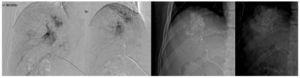

En agosto 2011, se realiza quimioembolización presentando respuesta parcial en el estudio de seguimiento a 3 meses. Se realizó QEIA nuevamente en diciembre 2011 (fig. 2). En seguimiento, se observa zona de captación en la periferia del tumor, en territorio subdiafragmático (fig. 3); en marzo del 2012 se decide realizar nueva QEIA. Por la localización de la zona con actividad, se realiza angiografía selectiva de probables ramas accesorias. En angiografía previa a la embolización, se identifica irrigación de la zona de actividad por parte de la arteria frénica derecha (fig. 4). Se realiza embolización blanda y ablación por radiofrecuencia (ARF). Última resonancia magnética dinámica de abril 2013, sin evidencia de activad tumoral (fig. 5).

Figura 2. Angiografía y QEIA a través de la arteria hepática derecha desde el tronco celíaco. Se observa captación del lipiodol y cisplatino por parte del tumor. Se identifica un defecto en la porción superior y lateral de la lesión.